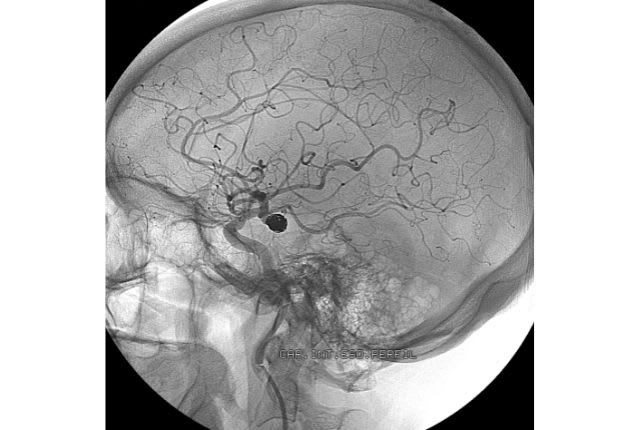

Pour diagnostiquer une rupture d’anévrisme, le spécialiste effectue des examens propres au type d’anévrisme suspecté : un scanner ou une IRM pour confirmer l’existence d’une hémorragie, une artériographie (ou angiographie) pour évaluer l’état des artères et situer précisément l’hémorragie, ou encore une ponction lombaire.

- le traitement endovasculaire : le chirurgien introduit un cathéter par l’artère fémorale jusqu’à l’anévrisme. Puis la poche d’anévrisme est bouchée par des spirales en platine appelées "coils". C’est la solution choisie dans 9 cas sur 10 ;